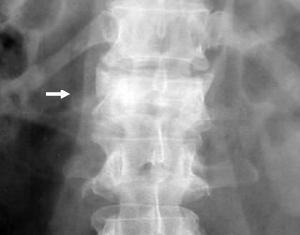

• Radiología columna dorso - lumbar

Rx. Columna dorso lumbar frente y lateral. muestra disminución del espacio vertebral L1, caracterizado por disminución de su altura, con fragmentación del cuerpo vertebral y escaso desplazamiento posterior.